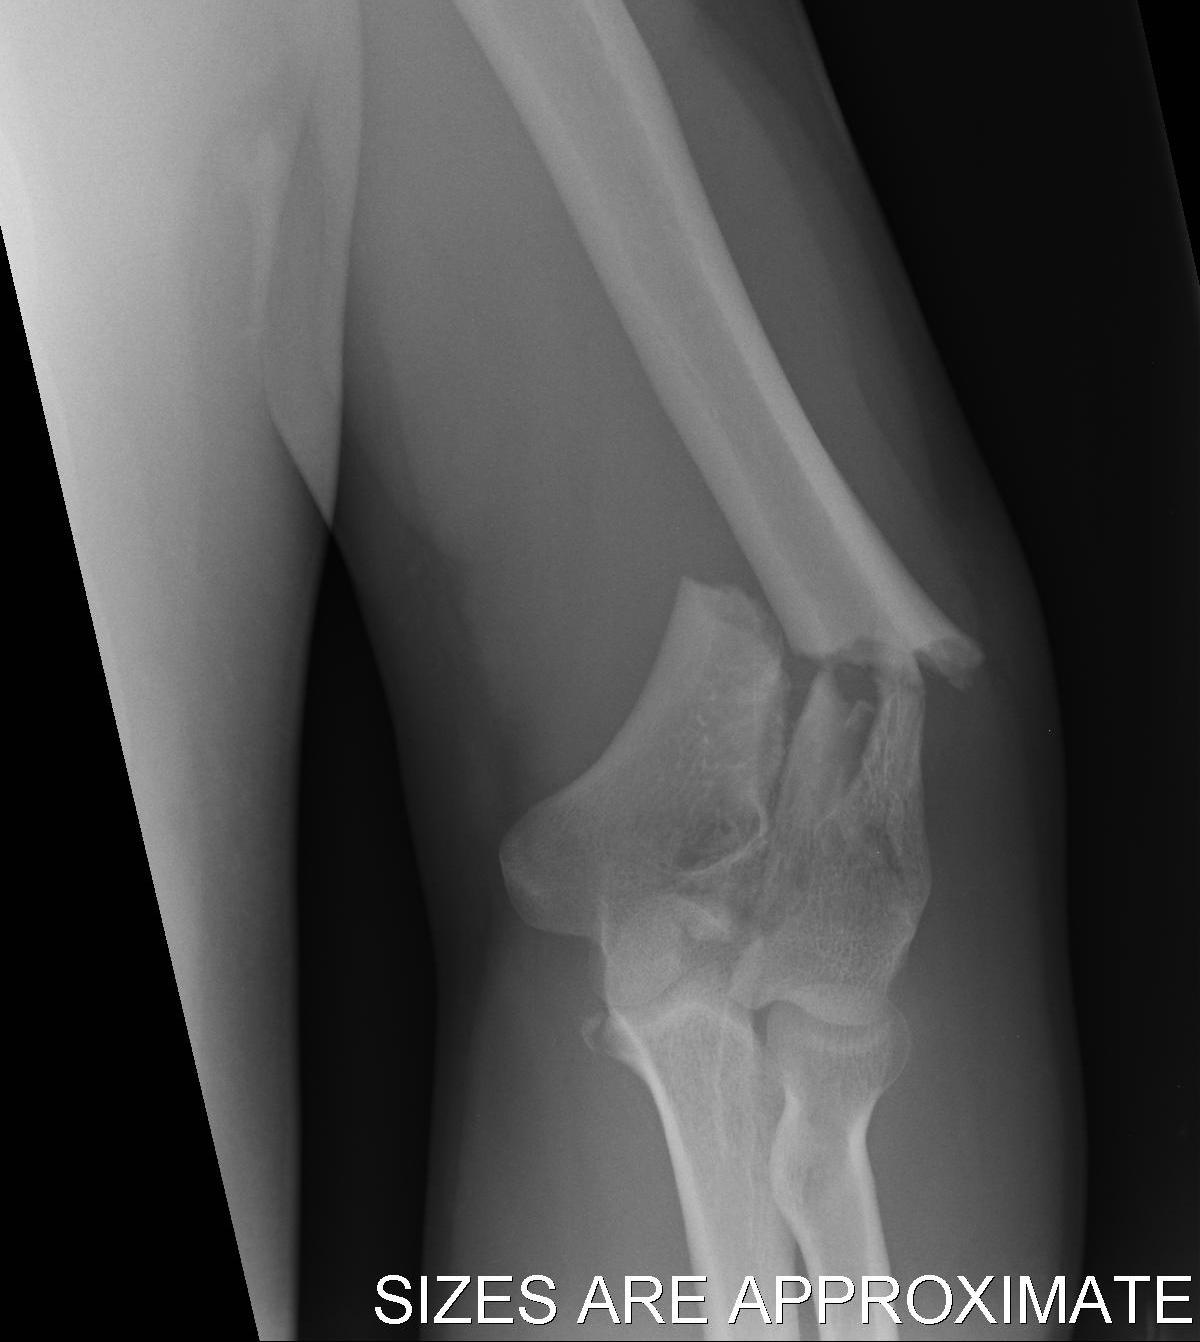

Bag of bones / nonoperative management

Initial injury in elderly patient

Elbow post treatment in cast

Indication

Patient elderly and not operative candidate

Technique

Initial rest in plaster then mobilisation

Results

- 40 "elderly and low demand" patients treated non-op

- 5 year mortality 40%

- 50% non union

- DASH score 38/100

- modest function, but avoids risks